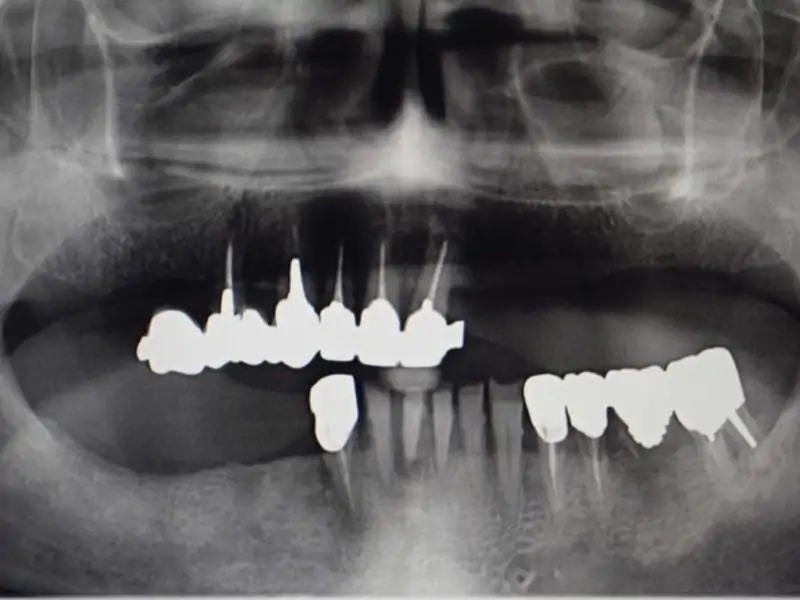

- Hygenic state: Very bad

The use of an arch to help praparing the ostheotomy in terms of inclination and positioning can be a great option to easily define the correct positionin for an all on four concept. This patient came with the request of stabilizing his own prosthesis so the treatment plan included the insertion of 4 implants on which we will use the suitable straight and angulated MUA to stabilize a retentive bar to retain a duplicate of the pre-existing prosthesis.

During the surgical session the preparation of the implant sites was made with the help of the guide arch that have to be inserted in the medial area and gives the indication on the correct positioning of implants for an all on four or all on six concept prosthesis. To minimize the tissue trauma we inseted the implants with a flapless surgery and with the use of stops to determine precisely also the lenght of the preparation. Right after the surgery the patient was left with healing screws on top of the implant and with his previous denture which we hollowed internally to avoid trauma on the implants. After 5 months the patient came back we took an impression an made a duplicate of the prosthesis which we used to build the bar to fix on top of MUAs and an internal framework and the retentive caps.